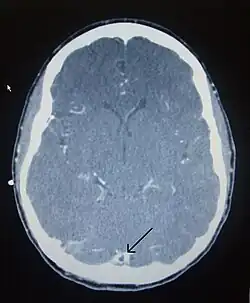

CT venogram showing a filling defect in the sagittal sinus (black arrow)

Computed tomography, with radiocontrast in the venous phase (CT venography or CTV), has a detection rate that in some regards exceeds that of MRI. The test involves injection into a vein (usually in the arm) of a radioopaque substance, and time is allowed for the bloodstream to carry it to the cerebral veins – at which point the scan is performed. It has a sensitivity of 75–100% (it detects 75–100% of all clots present), and a specificity of 81–100% (it would be incorrectly positive in 0–19%). In the first two weeks, the "empty delta sign" may be observed (in later stages, this sign may disappear).[11] The empty delta sign is characterized by enhancement of the dural wall without intra-sinus enhancement.[6]